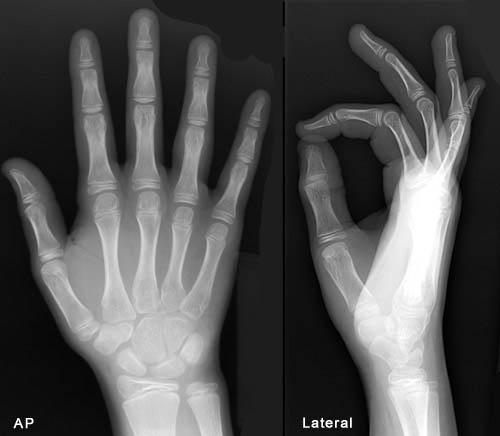

ПЕРЕЛОМ ЯКОЇ КІСТКИ І В ЯКІЙ ЇЇ ЧАСТИНІ ВИ БАЧИТЕ?

варіанти відповідей

ГОЛОВКИ HUMERUS

ДИСТАЛЬНОГО ЕПІФІЗА HUMERUS

ШИЙКИ FEMUR

ГОЛОВКИ FEMUR

ГОЛОВКИ RADIUS

ПРОКСИМАЛЬНОГО ЕПІФІЗА HUMERUS

ХІРУРГІЧНОЇ ШИЙКИ HUMERUS

АНАТОМІЧНОЇ ШИЙКИ HUMERUS